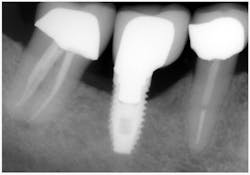

In May 2010, patient records indicated new bone around the implant. A radiograph taken May 2012 shows a gain of two threads of bone on the implant. In previous case studies bone stabilization has been documented for patients who use Perio Trays to apply a subclinical dose of tetracycline (3 drops) in short daily increments over the course of several months.Same implant, May 2012. Two threads affected, no suppurance.